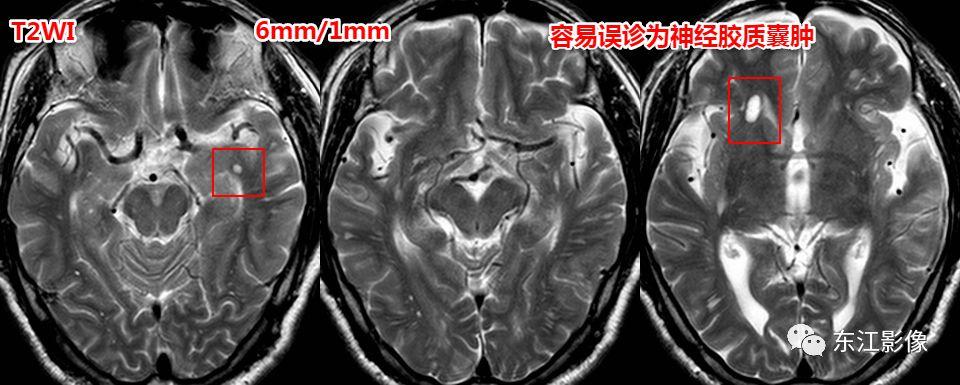

神经胶质囊肿

- 脑实质型神经胶质囊肿罕见,圆形或类圆形,无泪滴状或纺锤样外观;FLAIR边缘多呈稍高信号。

- 神经胶质囊肿多为单发,若多发时,两者之间,扩大的血管周围间隙更为常见。

容易误诊的扩大的血管周围间隙,详见: 即时学习 | 即时病例0022

容易误诊的扩大的血管周围间隙。

容易误诊的肿瘤样扩大的血管周围间隙。